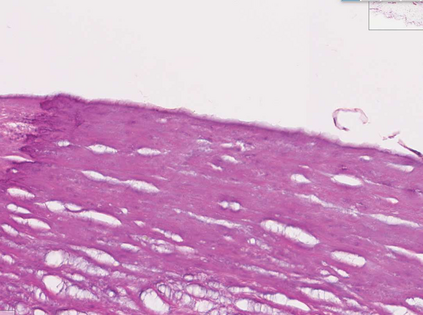

Coronary artery disease (CAD) is a cardiovascular condition with high morbidity and mortality. Intravascular optical coherence tomography (IVOCT) has been considered as an optimal imagining system for the diagnosis and treatment of CAD. Constrained by Nyquist theorem, dense sampling in IVOCT attains high resolving power to delineate cellular structures/ features. There is a trade-off between high spatial resolution and fast scanning rate for coronary imaging. In this paper, we propose a viable spectral-spatial acquisition method that down-scales the sampling process in both spectral and spatial domain while maintaining high quality in image reconstruction. The down-scaling schedule boosts data acquisition speed without any hardware modifications. Additionally, we propose a unified multi-scale reconstruction framework, namely Multiscale- Spectral-Spatial-Magnification Network (MSSMN), to resolve highly down-scaled (compressed) OCT images with flexible magnification factors. We incorporate the proposed methods into Spectral Domain OCT (SD-OCT) imaging of human coronary samples with clinical features such as stent and calcified lesions. Our experimental results demonstrate that spectral-spatial downscaled data can be better reconstructed than data that is downscaled solely in either spectral or spatial domain. Moreover, we observe better reconstruction performance using MSSMN than using existing reconstruction methods. Our acquisition method and multi-scale reconstruction framework, in combination, may allow faster SD-OCT inspection with high resolution during coronary intervention.